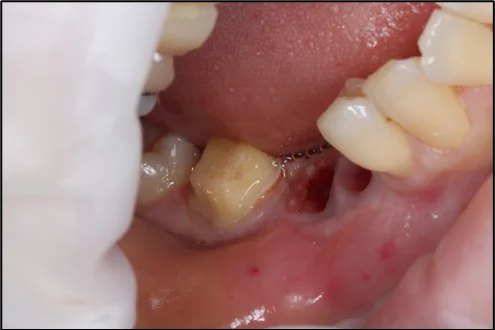

歯肉を切り出す部分に麻酔をかけて、移植を予定している部分の歯茎を切除して、サイズを計測します。

上顎から上皮組織と結合組織を採取

上顎から上皮組織と結合組織を採取します。麻酔をしっかりかけた状態で行うため、痛みはありません。もしも痛みや違和感がある場合はスタッフにお知らせください。

移植

移植部位の歯茎を剥離して、採取した上皮組織と結合組織を移植します。その後、歯茎を丁寧に縫合して手術は終了です。